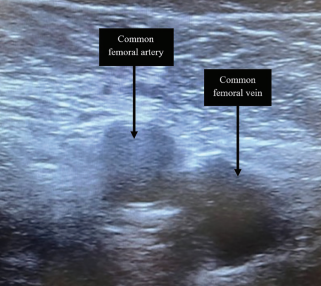

In our experience, the use of ultrasound-guided femoral access (Figure 1) and vascular closure devices (VCDs) have significantly mitigated access

site complications and have shown to have downstream effect on facilitating quicker discharge. Real-time visualization of the femoral vein significantly reduces the risk of arterial punctures and other vascular complications, particularly when using larger sheaths in ablation procedures. The ULTRA-FAST trial, amongst other studies, has demonstrated the advantage of ultrasound guidance in offering shorter puncture times, higher first-pass success rates, and fewer additional puncture attempts compared to conventional methods.5 It has also been associated with shorter patient ambulation time (2.0 ± 0.1 hours) compared to conventional methods (2.2 ± 0.6 hours), thus bringing patients closer to discharge earlier.6 The UNIVERSAL trial further demonstrated that ultrasound-guided femoral access, when combined with VCDs, results in significantly reduced risk of bleeding and vascular complications when compared to standard access techniques.7